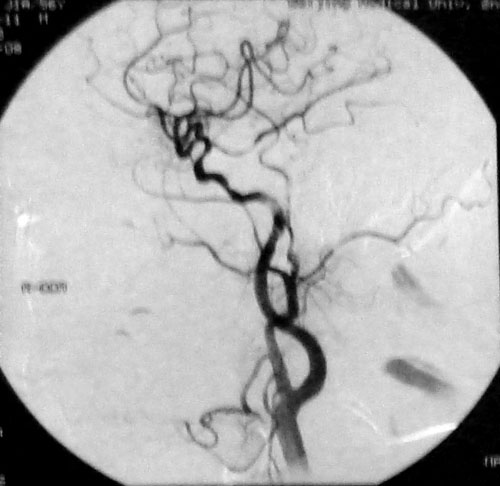

患者一:王某某,男性,52 岁,主因右眼视物不清7个月就诊。既往有II型糖尿病史14年,高血压史2年(3级),高甘油三酯血症。眼科检查:右眼玻璃体出血6个月,1个月前眼底有出血,视力仅0.2。左眼视网膜剥脱。1年前曾行白内障手术。房角3、6、9点新生血管。2008年9月8日在局麻下行颈动脉及眼动脉造影示:右侧颈内动脉起始部后壁斑块形成,局部管腔狭窄约50%,双侧眼动脉起始段狭窄约70%-80%。左侧血管虹吸部亦见狭窄。诊断:1、高血压病(药物控制后正常,极高危)2、2型糖尿病3、颈动脉粥样硬化症4、眼底出血5、高甘油三酯血症。(下图分别为其左侧和右侧颈动脉分叉DSA显像图)

该患者的颈内动脉管腔狭窄,影响了眼动脉的供血,行CEA手术取出斑块可以改善患者的症状。2008年9月28日,王某顺利接受了右侧颈内动脉内膜剥脱术。术后视力明显改善,右房角新生血管消退,视力提高,视物不清症状消失。半年后复查时其视力已恢复至0.4。

左侧颈动脉

右侧颈动脉